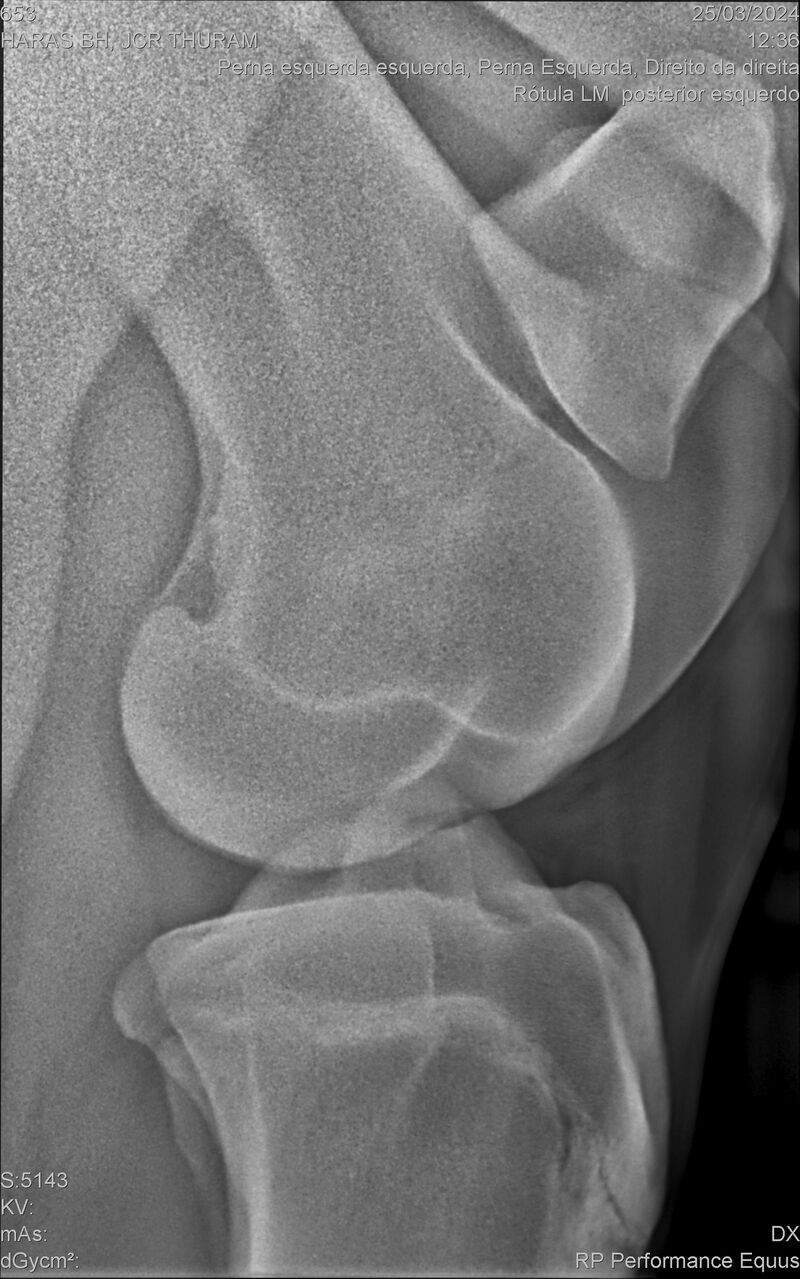

JCR THURAM

Raça: BRASILEIRO DE HIPISMO

Sexo: CASTRADO - CASTRADO

Nascimento: 10/01/2021

Altura Aproximada: 1,58

Pel.: CASTANHO

Registro: 27531-BH

Vend.: HARAS BH

Local : VINHEDO/SP